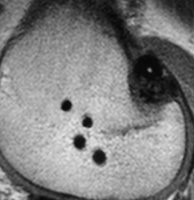

La cirugía de revisión del LCA actualmente es una técnica frecuente recibiendo habitualmente en nuestra práctica pacientes que han fracasado no sólo con la cirugía primaria sino que también en algunos casos con fracasos en cirugías posteriores de revisión. (Fig. 6 A-B y C)

![]() |

| Figura 6A: 3er revisión LCA(Nótese los túneles femorales anteriores y tibial posterior previos) | Figura 6B: Fijaciones con cross pin previas a nivel femoral | Figura 6C: Nótese el túnel tibial previo muy posterior |